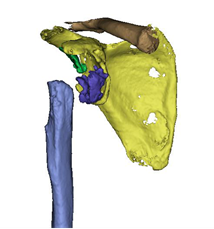

术前个性化定制3D打印-反肩关节置换假体,结合病情设计修补重建及定位点